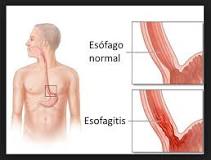

El Dr. Enrique Salcedo del Hospital 12 de Octubre nos habla sobre la Esofagitis.

La esofagitis es una inflamación que puede dañar los tejidos del esófago, el tubo muscular que lleva la comida de la boca al estómago.

La esofagitis puede hacer que sea doloroso y difícil tragar, y causar dolor en el pecho. Las causas de la esofagitis incluyen que los ácidos del estómago hagan reflujo al esófago, infección, medicamentos por vía oral, y alergias.

Los signos y síntomas comunes de la esofagitis incluyen:

- Difcultad para tragar

- Dolor al tragar

- Dolor en el pecho, especialmente detrás del esternón, que se presenta al comer

- Comida tragada que se atasca en el esófago

- Acidez

- Regurgitación ácida

En los bebés y los niños pequeños, particularmente aquellos demasiado jóvenes para poder explicar el malestar o dolor, los signos de esofagitis pueden incluir:

- Problemas para comer

- Falta de crecimiento

La mayoría de los signos y síntomas de la esofagitis puede ser causada por una variedad de trastornos que afectan el sistema digestivo. Visita a tu doctor si los signos o síntomas:

- Duran más de algunos días

- No mejoran ni desaparecen con antiácidos de venta libre

- Son lo suficientemente serios como para hacer que comer sea difícil

- Están acompañados por signos y síntomas de influenza, como dolor de cabeza, fiebre, y dolores musculares

Obtén cuidados de emergencia si:

Sientes dolor en el pecho que dura más de unos minutos

- Sospechas que tienes comida atascada en el esófago

- Tienes un historial de enfermedades cardíacas y sientes dolor en el pecho

- Sientes dolor en la boca o la garganta cuando comes

- Te falta el aliento o te duele el pecho, y esto ocurre poco después de comer

- Vomitas grandes cantidades, con frecuencia intensamente, tienes problemas para respirar después de vomitar o el vómito es amarillo o verde, se parece a los granos de café, o contiene sangre.